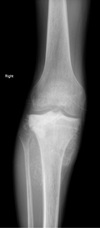

What age group is primarily affected by Ewing sarcomas?

10-25 years

71

What is the preferential location of Ewing sarcoma?

mid-diaphysis of long bones: - femur - pelvis - tibia - humerus - fibula

72

What are the radiographic characteristics of Ewing sarcoma?

- permeative/motheaten lytic destruction - long ZoT - cortical disruption (**saucerization** - rare) - laminated/spiculated periosteal Rxn - may extend to soft tissues - patho Fx (can look like osteomyelitis --> send to ER)

10 year old boy with lower leg pain and swelling. What is on your list of differential diagnoses in order from most to least likely?

Aggressive in kid = OLEO 1. Osteomyelitis 2. Osteosarcoma (metaphyseal) 3. Ewing sarcoma 4. Lymphoma

82

18 year old with pain and swelling of the lower leg. What is on your list of differential diagnoses in order from most to least likely?

Aggressive in kid = OLEO 1. Osteosarcoma (metaphyseal) 2. Ewing sarcoma 3. Lymphoma 4. Osteomyelitis (blastic = infection 4th)